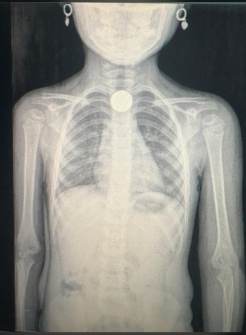

• Mesmo para objetos lisos (moedas), leve a criança ao médico para avaliação e exames (raio-X).

De acordo com a equipe médica, itens como moedas, pilhas de controle remoto e pequenas peças de brinquedos são frequentemente ingeridos de forma acidental. Ao dar entrada na unidade, a criança passa por avaliação na emergência e exames de imagem para identificar a localização do objeto no aparelho digestivo.

Ocorreu na sexta-feira (27), uma criança ingeriu uma moeda de cinquenta (50) centavos e a mesma ficou alojada na região do esôfago. A menina passou por avaliação médica de emergência e o objeto foi retirado no dia seguinte através de uma endoscopia. O Hospital Regional de Água Boa e a mãe da criança informaram ao departamento de jornalismo da Liberdade FM que a criança segue sem complicações.